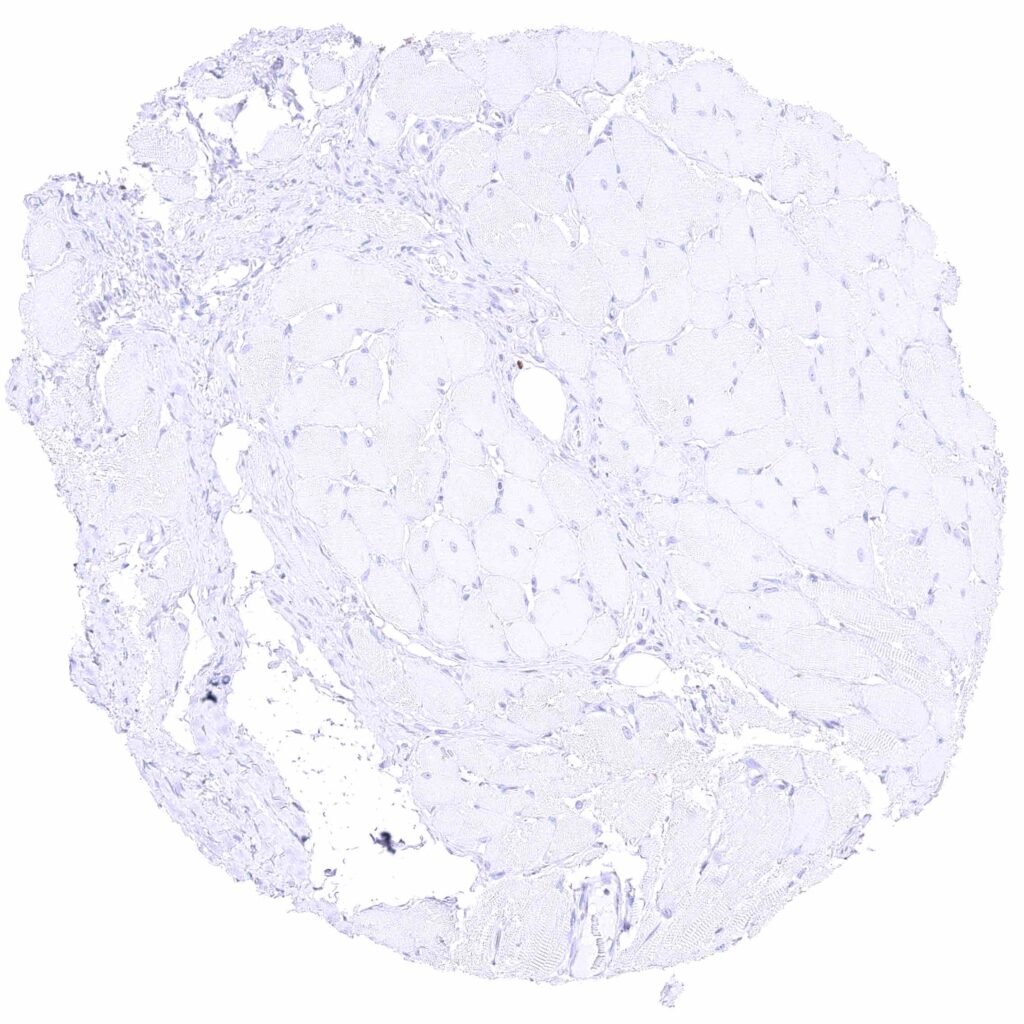

Fat